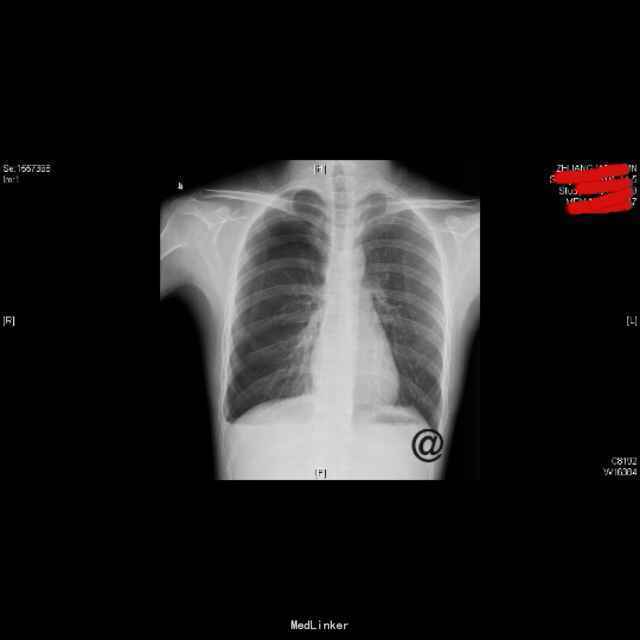

查体:右上肺呼吸音低,余无特殊;心脏、腹部查体未见异常。 辅查: (2015-10-27)行X平片(胸部)检查提示:右侧胸腔引流管置入后改变。 (2015-10-29)胸片:右侧气胸(肺组织压缩约10%),并右侧胸腔引流管置入后改变。 (2015-11-03)行CT(颈胸部CT)检查提示:1、右侧气胸,右侧胸腔积液,右侧胸膜增厚;2、右肺下叶良性硬化性小结节。 (2015-11-09)胸片胸部未见明显异常X线征象。 (2015-10-27)血生化:白介素-69.12ng/L、余无明显异常。 传染病四项、结核感染T细胞检测、大便、小便常规、血常规未见明显异常。 (2015-11-09)复查血常规:嗜酸性粒细胞百分数8.30%、余无明显异常。复查生化:未见明显异常。